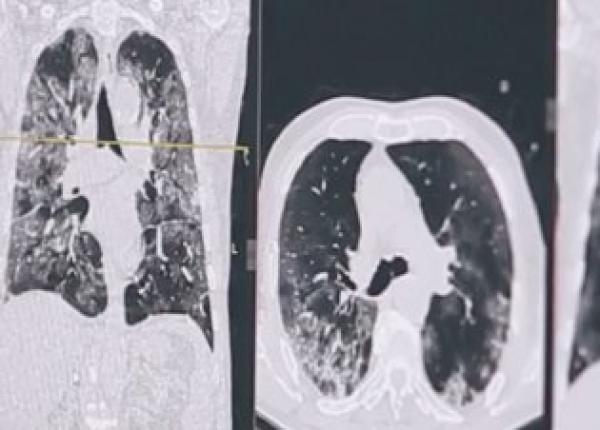

Cum arată plămânii afectaţi de COVID. Medic: Fără oxigen, aceşti oameni ar fi murit, cu siguranţă